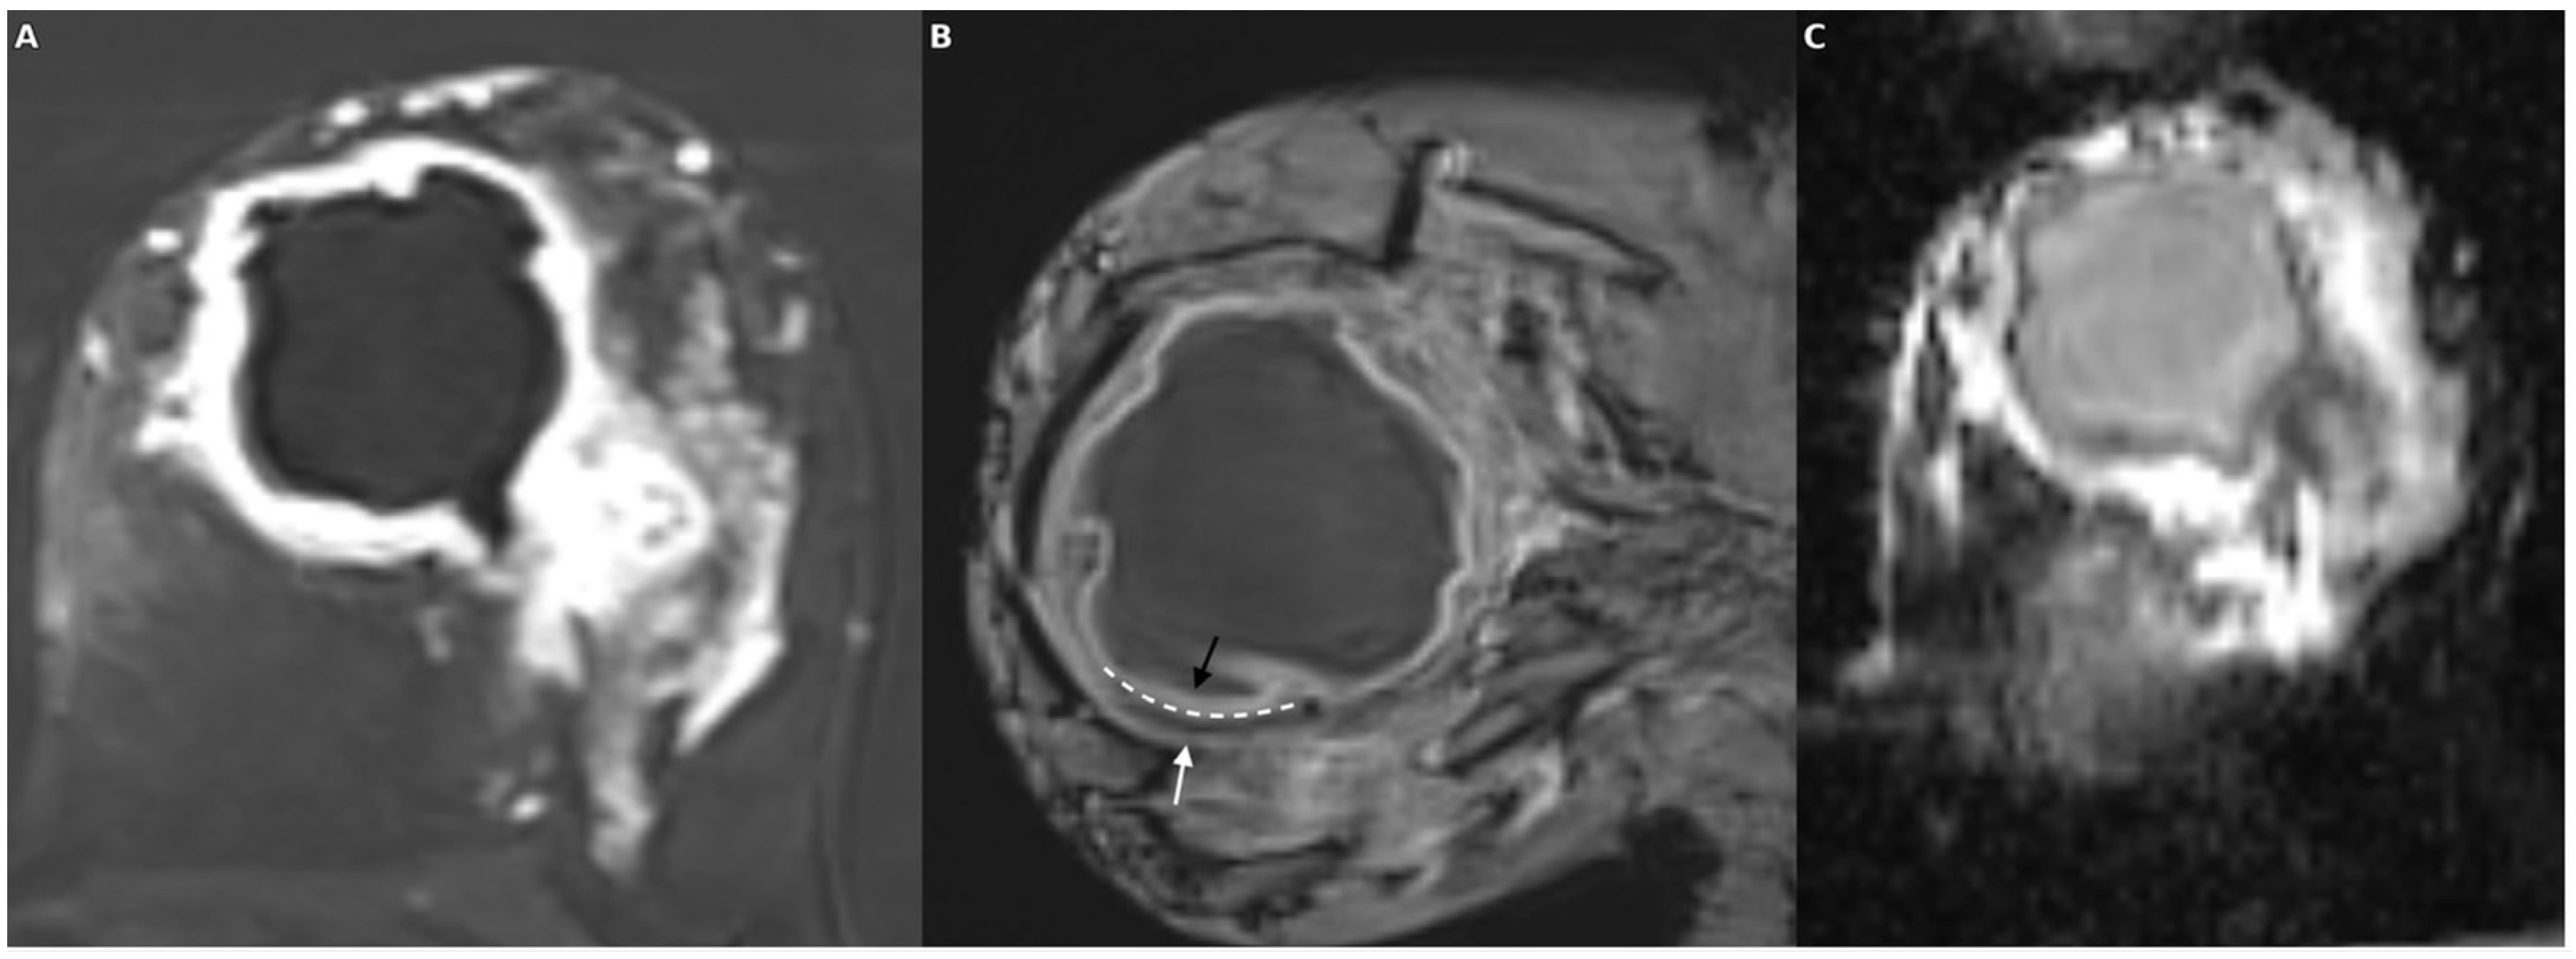

Figure 4. In a patient with ductal carcinoma in situ (DCIS) exhibiting necrotic features, the post-contrast subtraction image (A) shows a centrally necrotic mass with peripheral enhancement; the SWI sequence (B) demonstrates an irregular hypointense rim encircling the lesion with multiple intralesional susceptibility signal foci; and the ADC map (C) reveals relatively high values consistent with facilitated diffusion in the necrotic core.